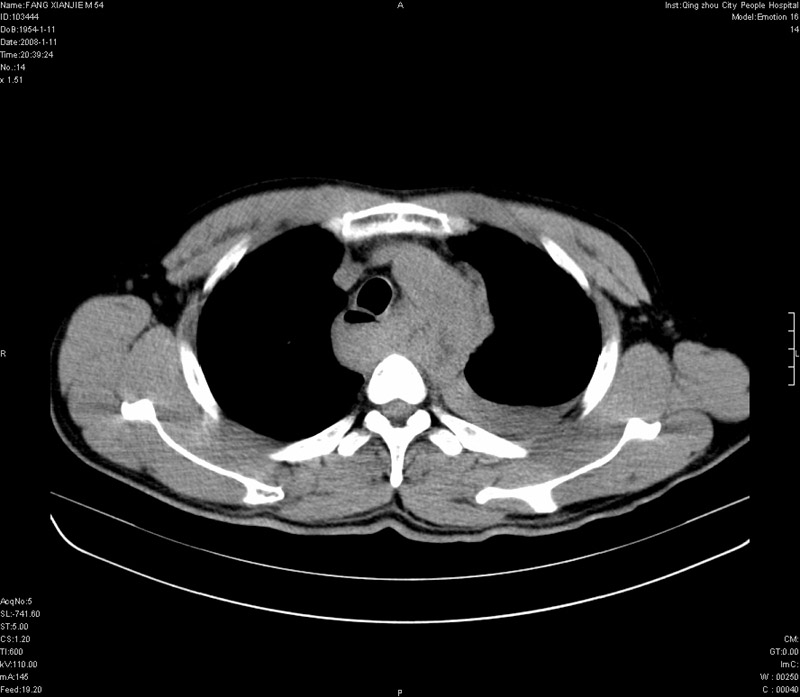

男性,40岁。胸部被车压伤伴胸痛1小时来院就诊。检查:一般情况尚可,血压110/80,胸部及上腹部压痛。结果在三天后公布。骨窗在横断位、冠矢状显示肋骨、胸椎、和胸骨未见骨折征象。

病人很危险啊,考虑胸主动脉破裂出血。

1)考虑为:胸主动脉破裂伴纵隔血肿,左侧胸腔积液(血)。2)胸骨柄骨折。

纵隔血肿,大血管破裂?左侧胸腔积血,胸骨柄骨折,冠状位示双侧第三肋骨折.

ct11308:胸部外伤1小时(证实病例) (2008-1-13 16:2)结果如下:病人入院后两小时后症状加重,8小时后在征得病人家属同意做了ct增强扫描。如下图。最终临床诊断:外伤性胸主动脉破裂并纵隔内血肿。由于有运动性伪影,胸骨在矢状面重建的图像似有骨折征,这是一种假象,我们称之为“假骨折”,这在多层ct重建中经常性遇到,必要时要结合横断图像鉴别之。现在,病人的一般情况较差,是否要手术家属尚有争议,如果手术修补,难度较大,需要专门预定制作固定支架。

当然,对于该病例,其它非重要的诊断还有:右侧少量气胸;左侧胸腔积液;左侧轻度肺挫裂伤。对于纵隔内血肿,我们曾经遇到过多例,也有怀疑主动脉的破裂,但是,均未得到具体出血部位的明确诊断。